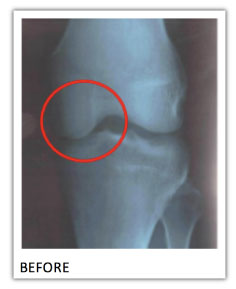

But that’s not all. Because these scientists decided to take X-RAYS of a few of the volunteers’ joints…

Look at the “BEFORE” image from just one of the study participants. Look how close the bones are together. That’s because the cartilage has naturally worn away over time from overuse.

But now look at the “AFTER” image.

See how much farther apart the bones are… with a clear, dark space in between?

As incredible as it is… the X-ray clearly shows…